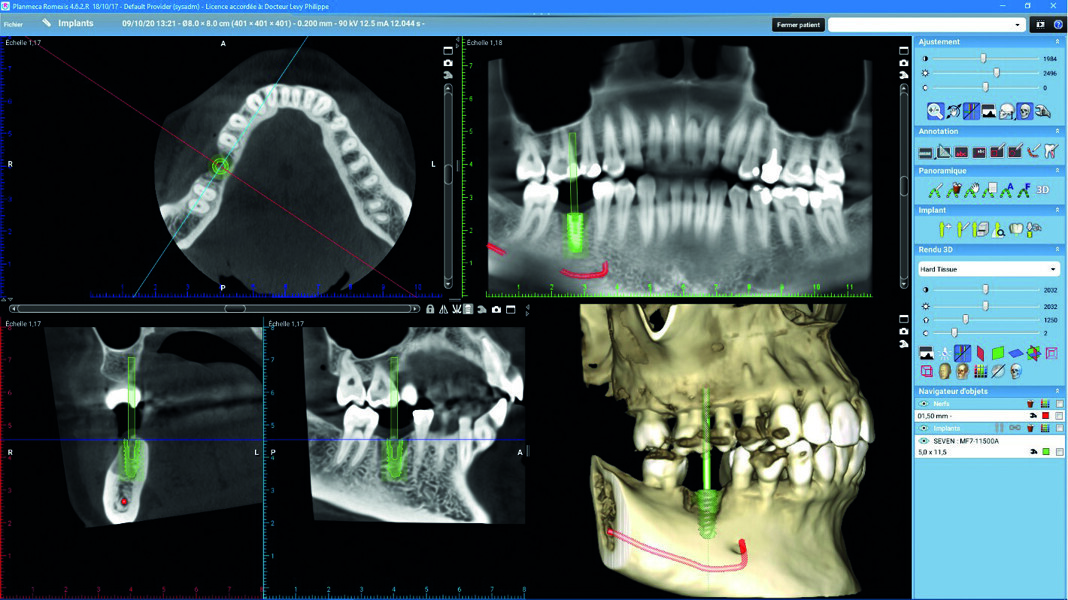

Planification implantaire numérique La marque, la taille et le diamètre des implants ont été choisis en amont sur indication du praticien, et peuvent être également géré par le laboratoire. Les implants sont positionnés selon l’axe prothétique idéal, tout en respectant la quantité d’os résiduel et les règles de sécurité (distance entre l’implant et les dents adjacentes, etc.).

Le bon positionnement de l’implant ainsi que son émergence au niveau de la future prothèse sont vérifiés (Figs. 4 et 5).

Fig. 4 : Planification implantaire.

Fig. 5 : Rapport chirurgical.

Le rapport chirurgical Un rapport chirurgical détaillé reprend la proposition de la planification faite par l’équipe du laboratoire de prothèse dentaire Crown Ceram, ainsi que les informations sur l’implant. Il est envoyé au praticien accompagné d’une vidéo 3D, pour bien visualiser le positionnement de l’implant.

Pose de l’implant Pose d’un implant Seven de MIS au niveau de la 46. Ces dimensions 5/11.5 mm permettent l’obtention d’une bonne stabilité primaire dans l’alvéole. Mise en place de la vis de couverture et fermeture du site.